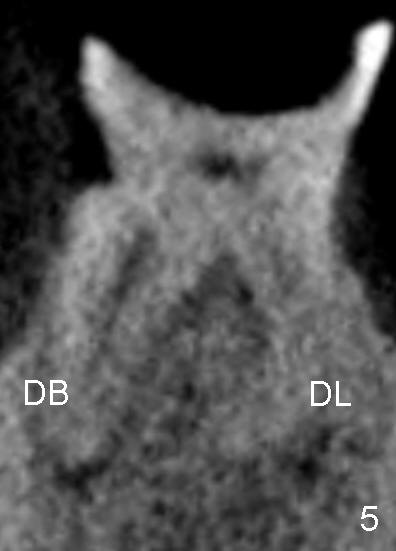

如果你的最终决定是"extraction", 我觉得“delayed implantation" is much better than "immediate implantation" for this case. 因为近中肉芽可能过多,炎症反应过大,initial stability可能会有问题。